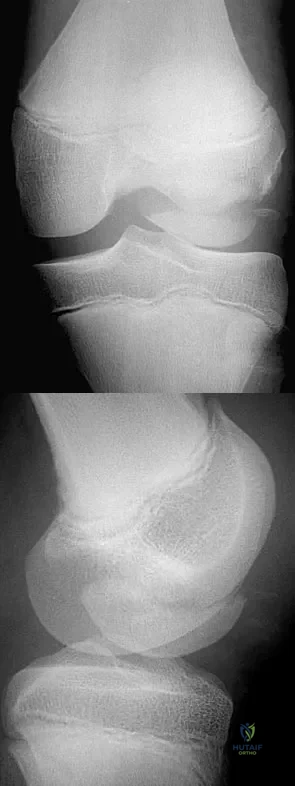

A 72-year-old woman has had progressively increasing pain in the right knee for the past 6 months. She denies any trauma and has no pain in any other joints, but she notes occasional swelling in the knee and a catching sensation. Figures 31a and 31b show the plain radiographs and Figure 31c shows the MRI scan. Treatment should consist of

Explanation

Which of the following primary prognostic factors best predicts the outcome of the knee lesion shown in Figure 22?

Explanation